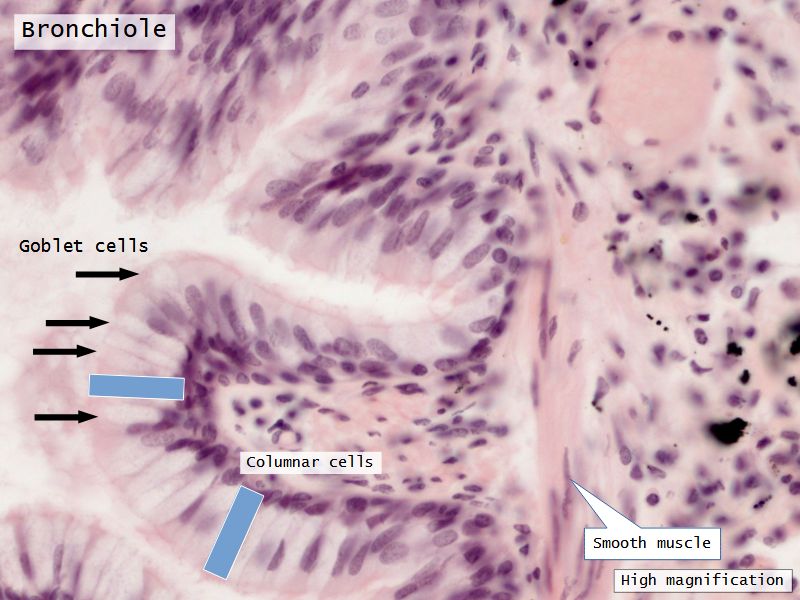

Fill in all the missing labels, and assess as you move through the slides. Answers on the down slide. It is important to do this using pen and paper, and not just glance through the images.